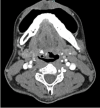

Vascular anomalies encompass a range of conditions affecting blood vessel development, categorized as tumors or malformations. Hemangiomas, the most common vascular tumors, involve abnormal endothelial cell proliferation, particularly in hemangiomas, which are prevalent benign tumors arising from mesenchymal tissue in the head and neck. They manifest as capillary, cavernous, or mixed types, affecting areas like the tongue and lips. Hemangiomas of the tongue base are notably rare, emphasizing the complexity of diagnosis and management due to their uncommon occurrence and potential for complications like bleeding. This report highlights a case of cavernous hemangioma of the tongue base, underscoring diagnostic challenges and management considerations. A Malay man in his late 30s, a nonsmoker and nondrinker, presented with a year-long history of intermittent globus sensation without associated symptoms like odynophagia, dysphagia, intraoral bleeding, or neck swelling. Flexible nasopharyngolaryngoscopy revealed a lobulated bluish mass at the right base of the tongue, prompting a provisional diagnosis of hemangioma. Contrast-enhanced CT suggested an irregular lesion with calcification, leading to MRI confirmation of a well-defined, non-muscle-invasive lesion that favored venolymphatic malformation rather than hemangioma. However, it was confirmed histologically as cavernous hemangioma after excision, where intraoperative findings aligned with initial preoperative clinical assessments.